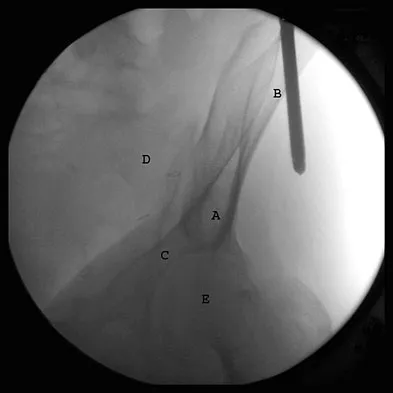

Figures 36a and 36b show the MRI scans of a patient who has shoulder weakness. What is the most likely diagnosis?

Explanation

A patient has right shoulder pain. Figure 1a shows a gadolinium-enhanced transverse MRI scan at the level of the coracoid. Figure 1b shows an arthroscopic view of the anterior structures from a posterior portal. These images reveal which of the following findings?

Explanation